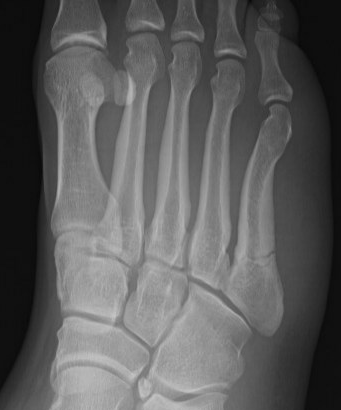

Base of 5th - Zone 1 / 2 / 3

Base Shaft Neck

Xray

Zone 2 fractures

Union of zone 2 fracture with nonoperative care

Progression to nonunion of zone 2 fracture with nonoperative care